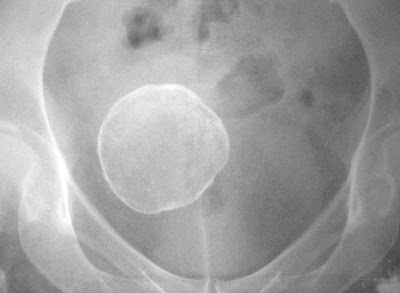

Foi realizado uma radiografia de quadril direito por queixas de dor nessa articulação, em uma paciente feminina de 55 anos, sendo descoberto incidentalmente uma grande calcificação arredondada projetada sobre a pequena pelve.

Foi realizado uma radiografia de quadril direito por queixas de dor nessa articulação, em uma paciente feminina de 55 anos, sendo descoberto incidentalmente uma grande calcificação arredondada projetada sobre a pequena pelve.Inicialmente foi levantada a hipótese de cálculo vesical; entretanto, a análise da radiografia pélvica demonstra claramente o contorno da parede lateral esquerda da bexiga, que sugere que a calcificação não está em seu interior. Imaginou-se, então, calcificação de origem ginecológica.

A paciente foi conduzida à sala de ecografia. A imagem mostra um corte longitudinal oblíquo, com a calficação em posição extra-vesical, posterior e à direita da bexiga.

Tratava-se de um mioma calcificado na porção fúndica de um útero anteversofletido, levemente lateralizado à direita.